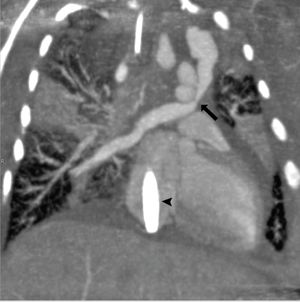

Supracardiac total anomalous pulmonary venous return (TAPVR) case study: A term newborn infant developed profound respiratory distress shortly after birth. After a negative echocardiogram, venovenous ECMO was performed. A cardiac CTA was requested, but complicated by the fact that the patient was on ECMO.